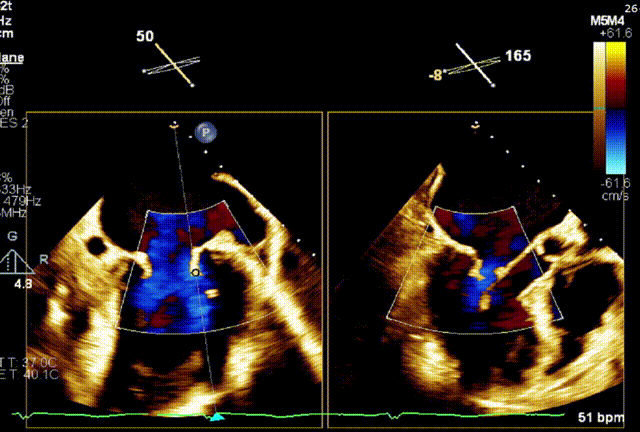

术前TEE评估

经食道超声提示,患者二尖瓣P1 commissural脱垂、腱索断裂合并重度反流(Carpentier II型/DMR4+)。

二尖瓣后瓣环明显钙化;主动脉瓣轻度钙化;三尖瓣中度功能性反流(FTR2+)。左房明显扩大;左室壁非对称性肥厚,以室间隔基底段肥厚为著(HOCM)。左室整体收缩功能正常。

二尖瓣环AP径33mm,二尖瓣后瓣环明显钙化,房间隔拟穿刺高度40mm;二尖辦脱垂宽度5.7mm,脱垂高度7.7mm,二尖瓣1区前叶长度29mm,后叶长度19mm,二尖瓣2区前叶长度23mm,后叶长度14mm,MVA=4.0cm²。

术前1区X-Plane反流情况